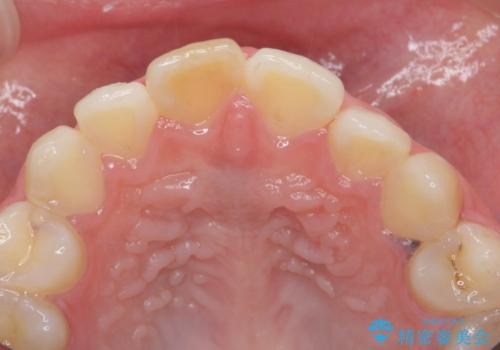

前歯の変色をキレイに セラミッククラウン審美治療

- 前歯の変色が気になる、見た目を改善したい!と審美性の回復を希望され来院されました。

ホワイトニングでは、周囲の歯との色調になじむほどには白くできないため、ジルコニアセラミッククラウンを用いて審美性を回復します。

周囲の歯の色調に調和した審美性の高いセラミッククラウンを製作することができました。